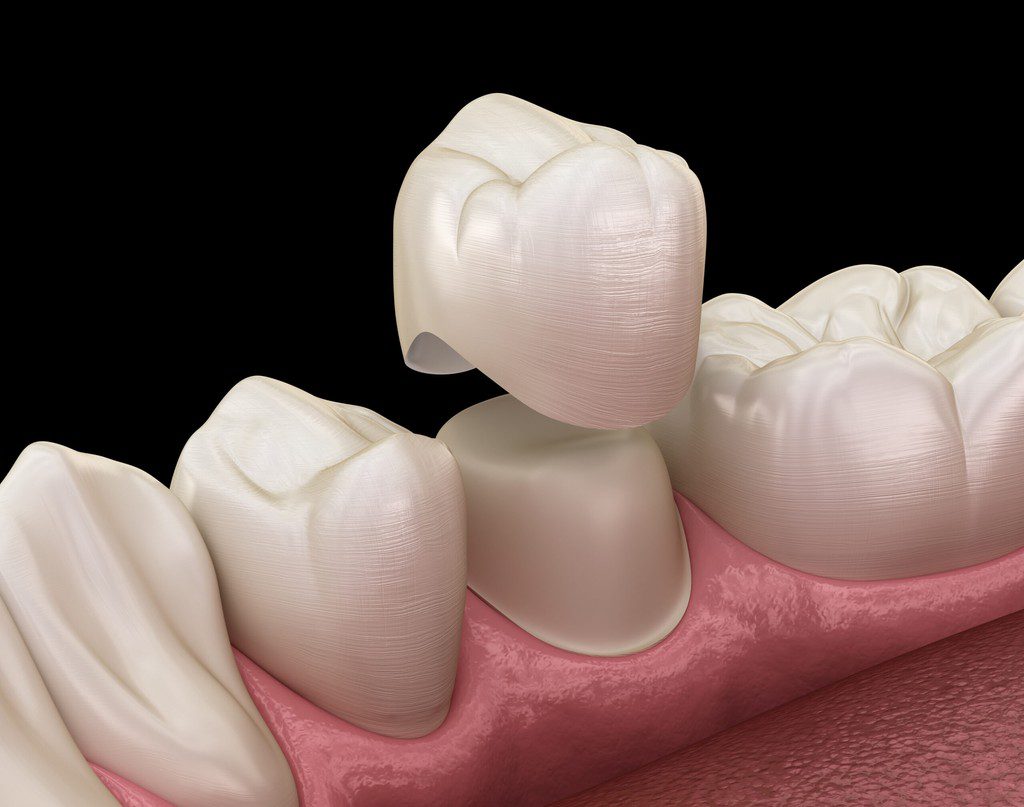

Dental Crowns

A dental crown procedure is a rather simple dental treatment but one that requires a great deal of precision and expertise. All our procedures begin with an in-depth consultation.

Next, a cast of the patient’s teeth is taken to develop dental crowns perfectly customized according to the patient’s unique dental and bone structure. We want the dental crown to cover the affected tooth/teeth completely and blend naturally with the rest of the teeth. After the first appointment with us at our Katy dental clinic, the patient may be provided with temporary crowns until the time their final dental crowns are ready.

During a second appointment, the final and permanent dental crowns are capped over the affected teeth to cover them completely and are bonded with the help of a dental adhesive. We will use a local anesthetic at this stage if needed. Our Katy dental specialists ensure the dental crown process is fast, safe and pain free.